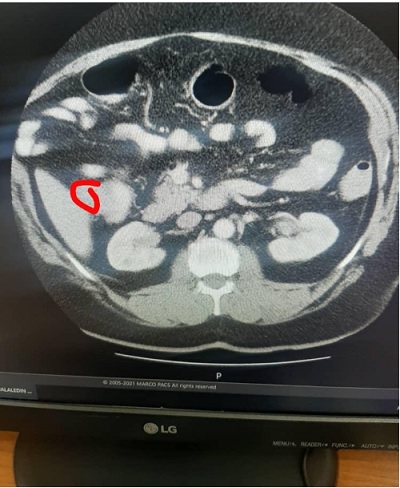

أنجزنا الأمر ورجعت إلى غرفتي الخاصة، وفي يوم الثلاثاء 111 جاء الدكتور ساسان وأبلغني بأن التصوير المقطعي أظهر وجود ورم على جدار القولون بحدود أربعة إلى خمس سنتمترات، وأراني صورته بالفعل، مشيراً إلى أنهم يحتملون أنّه هو الذي تسبب بذلك التضيّق في القولون، وأنّ الأمر لا زال تحت الدراسة لتشخيص العمل المطلوب، مع التأكيد بأن استمر على عدم تناول أي طعام للحاجة إلى المزيد من عمليات الناظور.

وما أن حلّ الظهر حتى وجدته قد عاد ومعه مجموعة من المعنيين ومعهم الدكتور بهنام وحالة الارتباك تلوح على وجوههم، فأوجست في نفسي أنّ أمراً أقلقهم وأهمّهم، وحاول الدكتور ساسان أن يخفف وطأة الخبر متصوّراً بأني قد أتألم أو أصاب بالذعر لو أنه أخبرني، ثم أخبرني بأنّ الصورة المقطعية تشير إلى وجود غدّة هي التي تسببت بتضييق القولون، وهذه الغدّة يحتمل أن تكون خبيثة، وعليه يجب أن يأخذوا خزعة منها لفحصها من أجل تحديد العلاج الفوري لها، كما أنهم يجب أن يلاحظوا إن كانت منتشرة أو لا زالت كامنة، وبطبيعة الحال أكّد على الاستمرار بعدم الأكل والإسراع بأخذ البودر الخاص بتنظيف الأمعاء وتفريغها، لأنهم سيستبدلون الناظور بواحد آخر أنحف من الذي سبقه، وقد حدد الساعة الرابعة كموعد لإجراء عملية جديدة للناظور.

حلّ يوم الأربعاء 121 وفي وقت قريب من الظهر جاء الدكتور ساسان والسرور قريب من وجهه، قال لي هناك أمر غريب، فالناظور لم يجد الورم، رغم أن الدكتور بهنام يقول أنه أورد الناظور ثلاثة مرات في ذلك الموضع الضيق، بل وجد أن الضيق قد زال في ذلك المكان إلى حد ملحوظ، فتوجهت في قلبي لأبي الأحرار مسلّماً ومعظّماً، وقلبي يلهج مضطرباً وعيني تنازع من أجل أن تذرف الدموع عرفاناً ومحبة، ولكن الدكتور أخرجني من حالتي حينما قال بأننا نحتاج إلى فحص الرنين كي نتأكد من الحالة، وبعد الرنين يمكن أن تخرج من المستشفى، قلت له: أين غدت الغدة؟ فقال: لا أدري، الأطباء لم يتفقوا على رأي، ولكن القدر المتيقن أننا لم نجد الغدة التي رأيناها في التصوير المقطعي، والجواب النهائي سيفصح عنه الرنين المغناطيسي، فقلت له: أنا أدري! نظر مبهوتاً ولكنه لم يعلّق.

صبيحة الخميس اتصل الدكتور ساسان وهو يتحدث عن فصّ الملح الذي ذاب! قال ذلك وهو يلهج بالصلاة على محمد وآل محمد، وكنت أخفيت عليه قصة أثر القبر الشريف ولم أخبره بها، كما لم أخبر أي أحد بها، تكلمت معه فقال لي: إن الدكاترة منذهلون من هذه الحالة ولم يجدوا لها تفسيراً، فالتصوير المقطعي والناظور الأول يؤكد وجود الغدة، ولكن الناظور اللاحق والرنين المغناطيسي يؤكدان عدم وجودها، حتى أنّ بعض الدكاترة قرر أن يعود للكتب المختصة ليبحث عن سر ذلك. فقلت له: لو كنت مكانهم لما بحثت في الكتب، فسألني عن السبب، فقلت له: إننا أتباع أبواب النجاة وملاجئ الرحمة ومعادن الحلم والكرم، فلو تعلقنا بحبائلهم لأغنونا عمّا سواهم، ثم حدّثته عن أثر القبر الشريف، وعن لحظة الألم التي داهمتني والتي تيقنت وقتها بأنّ هذا الأثر قد سرى مفعوله. بين بكائه وفرحته الشديدة لكون هذا الأمر كان يسمع عنه إلا أنه لم يصادفه كما حصل الآن، قال بأنه يجب أن يخبر الأطباء بذلك، فتوادعنا مع تأكيدي أن يبلغ الدكتور بهنام بما جرى، فقال ضاحكاً: هو أوّلهم.